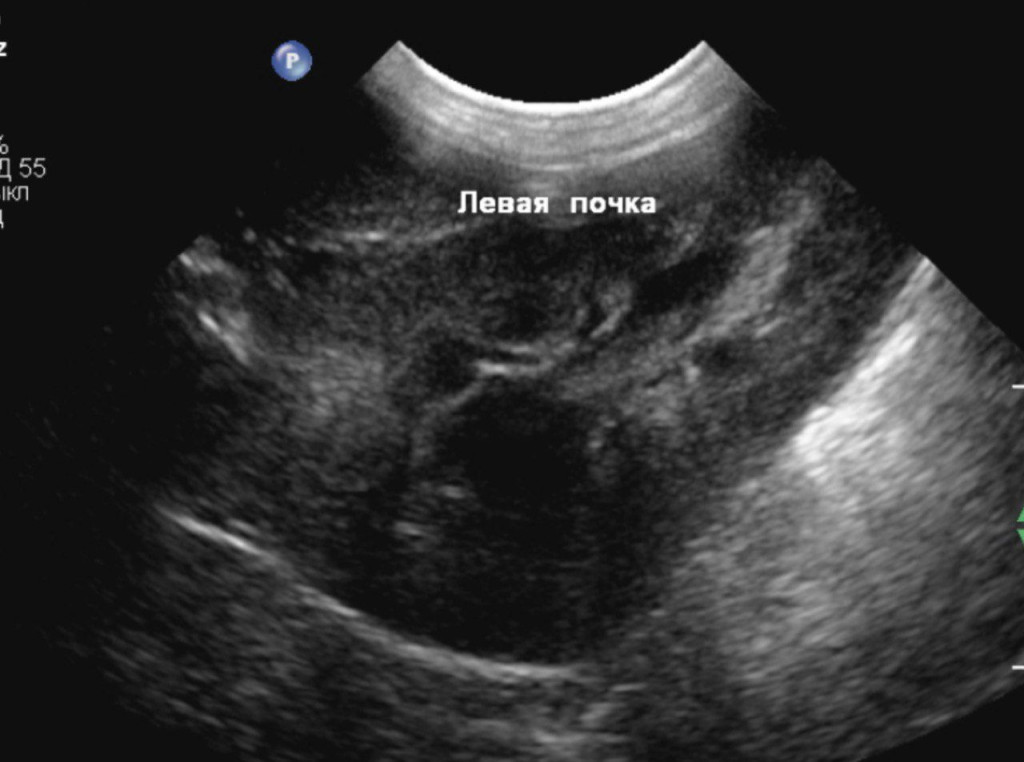

- отсутствие структурных изменений в почках (рис. 4).